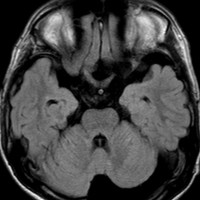

幼児の視路の毛様粘液性星細胞腫です。T2強調画像(左側)で白く高信号に写るのが特徴です。ガドリニウム増強ではまだらになっていますが,均一に真っ白に高信号になることも多いです。乳幼児のものは,ドロドロに柔らかい腫瘍です。

whole optic pathway pilocytic astrocytomaとは

両側の眼窩内視神経から視交叉、視索,外側膝状体,内包後脚,視放線近位部までが腫瘍化しています。FLAIRで高信号で,不規則にガドリニウム増強されます。これを手術摘出したり生検したりしても無駄です。放射線治療は不可能であり治療方法は化学療法のみです。